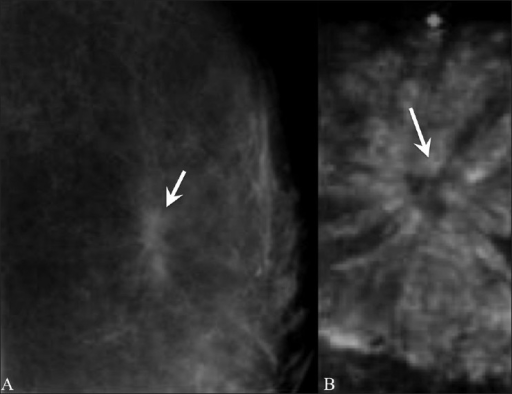

Sclerosing adenosis

This condition is caused by an overgrowth of tissue in the breast lobules. As with radial scars, sclerosing adenosis is generally found on mammogram, as the person will be asymptomatic. It resembles cancer on mammogram and will require further investigation. No treatment is required, but the condition is associated with an increased risk for developing breast cancer.